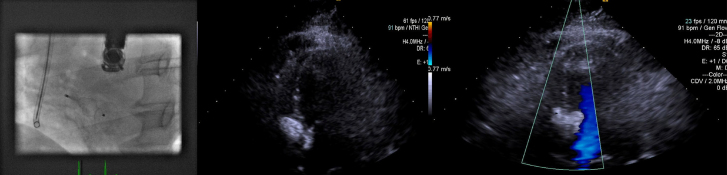

室间隔缺损(VSD)是当今世界上最常见的先天性心脏病之一。虽然大多数是自发关闭,经导管室间隔关闭是一种常见的选择,有症状的患者在成年合适的解剖结构。虽然经食管超声心动图(TEE)和心内超声心动图是该手术最常见的成像方式,但在TEE图像不佳的患者中,经胸超声心动图(TTE)可作为可靠的替代方法。在这里,我们报告了一例肺动脉高压合并肌肉性室间隔缺损的成年患者,由于TEE图像不佳,经皮采用二维TTE缝合。

Ventricular septal defect (VSD) is one of the most common congenital heart diseases worldwide today. Although the majority close spontaneously, transcatheter VSD closure is a common option for symptomatic patients with suitable anatomy in adult age. Although transesophageal echocardiography (TEE) and intracardiac echocardiography are the most common imaging modalities for the procedure, in patients with poor TEE images, Transthoracic echocardiography (TTE) can be used as a reliable alternative. Here we present an adult patient with pulmonary hypertension associated with a muscular VSD which was closed percutaneously using 2-dimensional TTE because of poor TEE images.